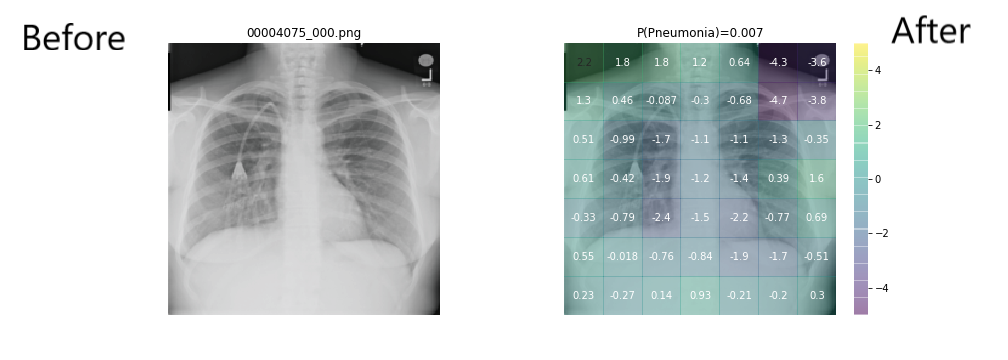

It that takes patient chest X-ray image as input and outputs the probability of a pathology like pneumonia.